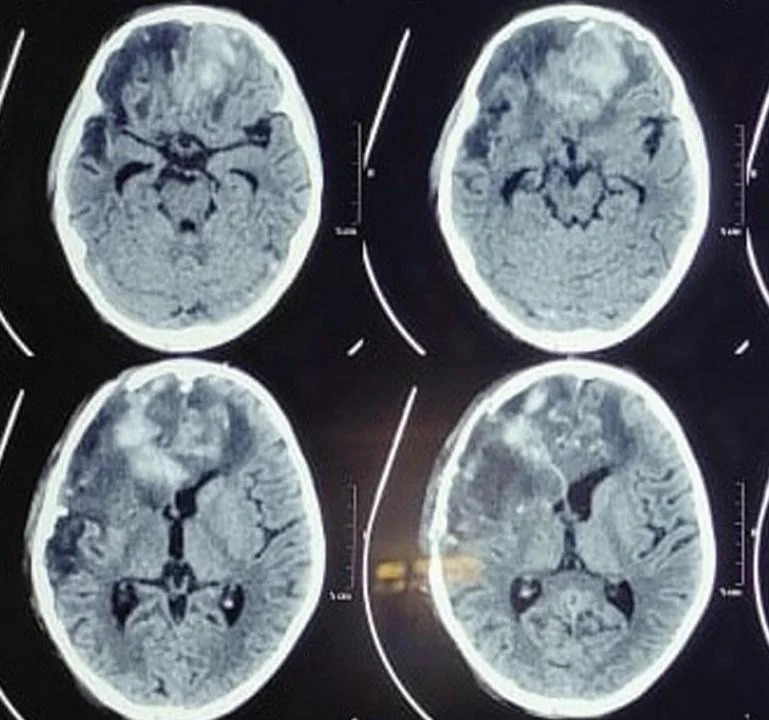

Fig 3: Preoperative computed tomography showing B/L frontal contusion with gross edema, subarachnoid hemorrhage, and intraventricular hemorrhage.

A noncontrast computed tomography (NCCT) head showed B/L frontal contusion with gross edema, subarachnoid hemorrhage, and intraventricular hemorrhage. There was fracture of bilateral frontal bone extending to right parietotemporal bone (►Fig. 3). A diagnosis of penetrating compound head injury by agricultural fan blade was made. Patient was taken to operating room (OR), where after painting and draping, the wound was irrigated with normal saline. The herniated brain was removed, securing hemostasis with surgical and Bovie cautery. Lax duraplasty was done with harvested pericranium and wound closed in layers (►Fig. 5).